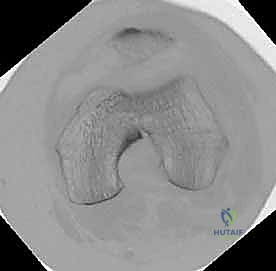

المرحلة الثالثة: إرجاع العظم (Reduction)

هذه هي الخطوة الأكثر أهمية. يقوم الدكتور هطيف بإعادة القطع العظمية المكسورة إلى مكانها التشريحي الأصلي. إذا كان الكسر ممتداً داخل المفصل، يتم تثبيت السطح المفصلي أولاً باستخدام مسامير دقيقة لضمان سطح أملس يمنع الاحتكاك والخشونة مستقبلاً.